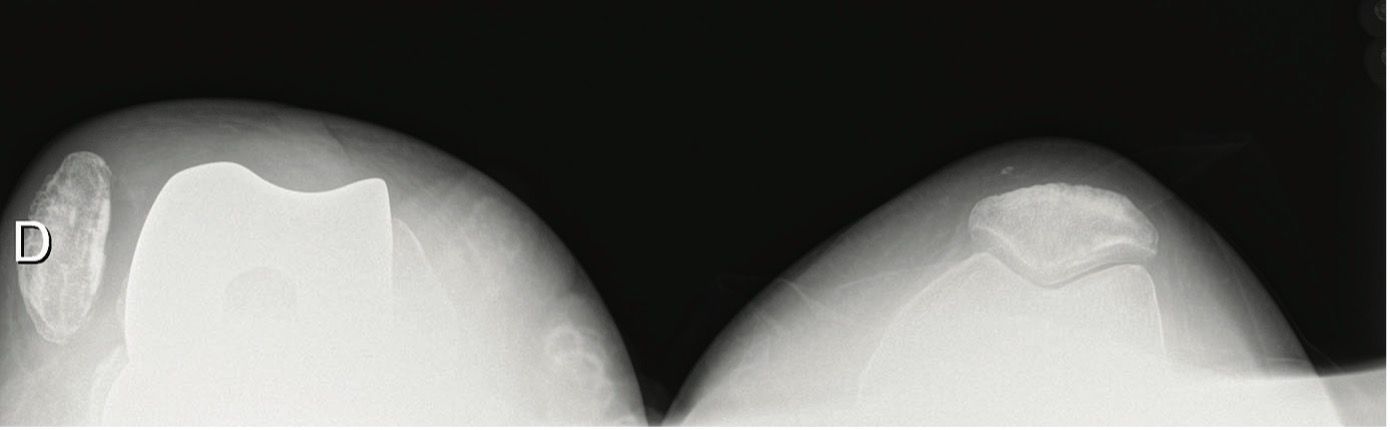

The accompanying articles address a broad spectrum of knee arthroplasty challenges. Infection management is examined through two-stage TKA protocols for active septic knee arthritis with severe chondrolysis and treatment of infected unicompartmental knee arthroplasty. Technical optimization is addressed in key steps for total knee arthroplasty and the role of MPFL reconstruction in TKA. Comparative outcomes between high tibial osteotomy and unicondylar arthroplasty and a critical appraisal of robotic knee surgery further enrich this issue.